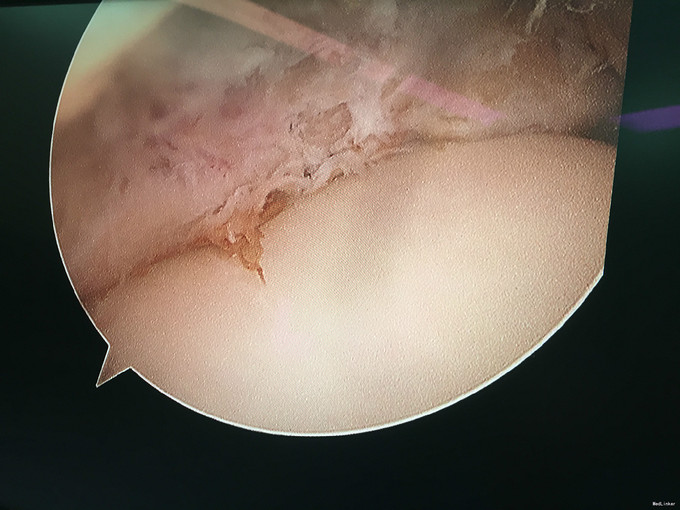

入院诊断:右踝前方撞击综合征、右距骨骨软骨瘤、右踝滑膜炎 治疗:入院完善术前检查后行右踝关节镜下滑膜清理+前方撞击成形+距骨骨软骨瘤切除。

随访:患者术后6周,踝关节活动度恢复正常,正常行走。 讨论:本病例系关节镜结合切开手术的范例,术中见踝关节内滑膜非常像色素沉着绒毛结节性滑膜炎,但未得到病理证实。还需要长期的随访来判断。